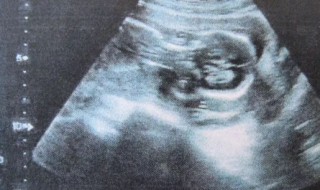

1、进行B超检查大约10-15分钟左右的时间就可以的,如果病情比较复杂,检查的时间可能会久一些。

2、如果做B超检查的部位比较多,检查的时间也会久一些,主要是根据具体情况才能够完全明确。通常不需要太长时间,通过B超检查可以更好的明确具体病情。